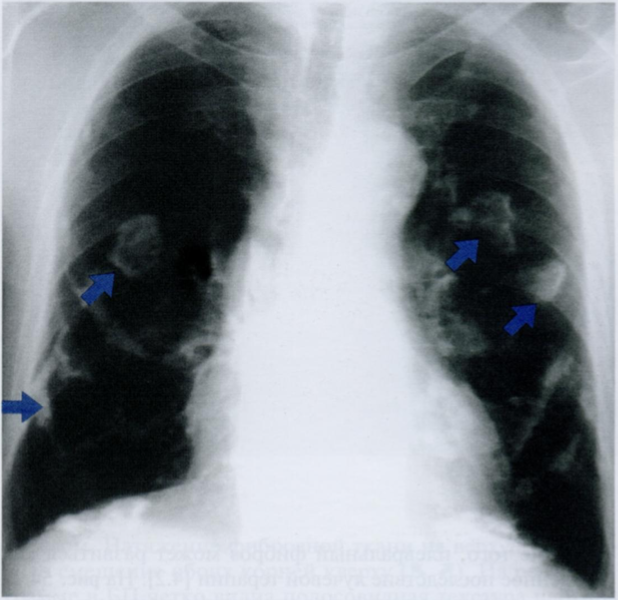

На снимке отмечены двусторонние обызвествления плевры (косые стрелки), которые проецируются посреди легочного поля из-за их расположения на передней и задней поверхностях грудной стенки. Эти обызвествления не следует принимать за внутрилегочные образования. Кроме того, утолщение плевры (горизонтальная стрелка) определяется на латеральных поверхностях грудной стенки с обеих сторон

Наличие ограниченного утолщения плевры размером более 1 см должно вызвать подозрение об опухоли.

Утолщение париетального и висцерального листков можно дифференцировать при помощи УЗИ или рентгеноскопии в реальном масштабе времени: образования висцеральной плевры повторяют дыхательные движения легких, тогда как в случае расположения на париетальной плевре или в самой грудной стенке происходит повторение движений ребер.

Если толщина плевры превышает 3 мм, необходимо провести компьютерную томографию. КТ-исследование позволяет отличить патологию плевры от изменений в прилегающих тканях.